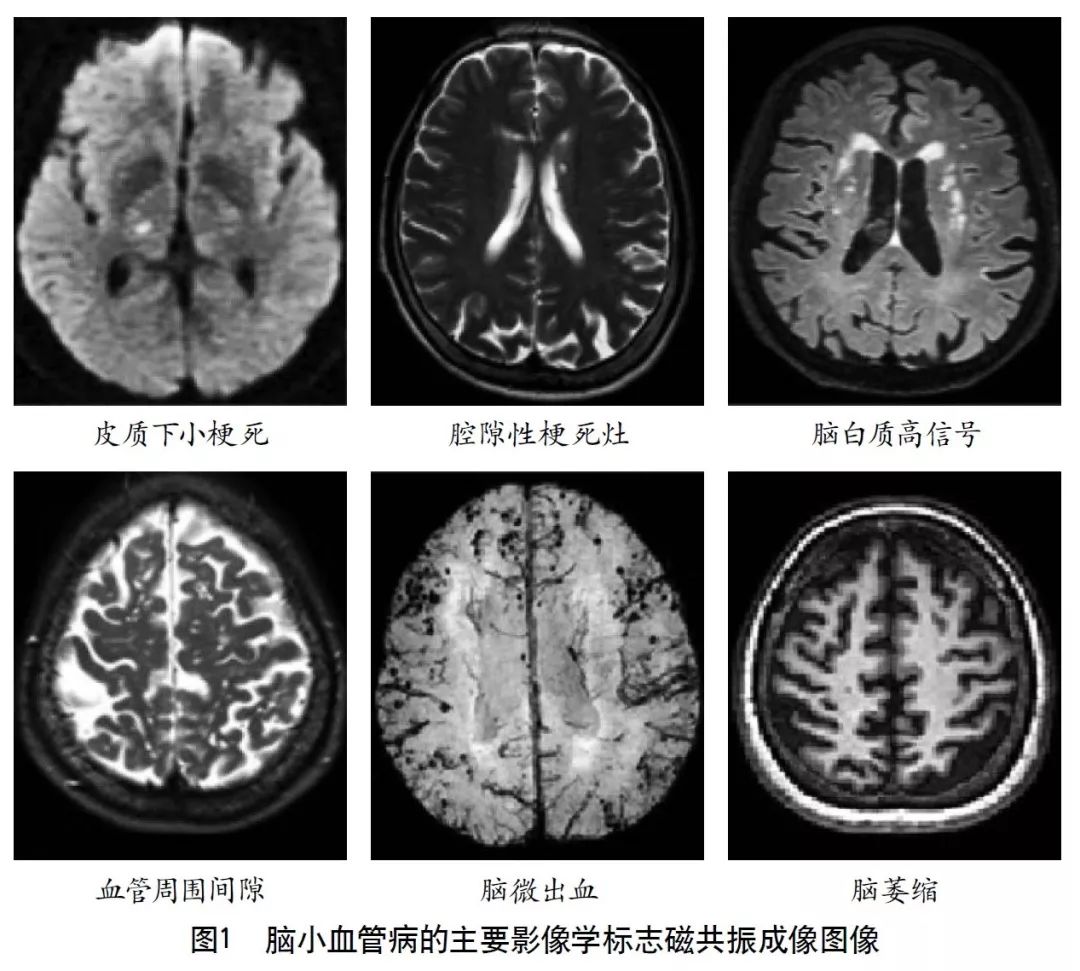

2011年,美国医学研究委员会、德国神经退行性疾病研究中心和加拿大卫生研究院共同建立了神经退行性疾病精英中心。2013年,该中心的核心专家组成员共同撰写了CSVD的共识指南,确立了代表CSVD的6种关键性损伤的神经影像学标志(图1),分别是近期皮质下小梗死、假定血管源性的腔梗灶、假定血管源性的白质高信号、PVS、脑微出血和脑萎缩。现将CSVD影像表现的相关影像技术介绍如下。

MRI是目前检测CSVD最重要的工具。常规检查序列包括:T1加权成像(T1WI)、T2加权成像(T2WI)、弥散加权成像(DWI)、FLAIR、梯度回波序列(GRE)、磁敏感加权成像(SWI),此外还有弥散张量成像(DTI)、静息态功能磁共振等。而MRI上可观察到的CSVD影像学改变主要有如下几种。

4.2.1 近期皮质下小梗死

根据2013年共识指南,近期皮质下小梗死的定义为:脑内一条穿支动脉供血区域的近期梗死,且伴有近期脑损伤一致的影像学特征或临床综合征表现。近期皮质下小梗死多发生在半卵圆中心、放射冠、基底节区、脑干等部位,MRI图像上呈T1WI低信号、T2WI高信号、FLAIR高信号、DWI高信号和GRE等信号。其轴位切面显示急性期梗死直径<20 mm,冠状位或矢状位可以>20 mm。

4.2.2 假定血管源性的腔隙灶

假定血管源性的腔梗灶定义为:圆形或卵圆形,直径为3~15 mm,分布于皮质下,充满与脑脊液相同信号,与穿支动脉供血区陈旧梗死或者出血相关。通常在FLAIR上表现为中心脑脊液样低信号,周边围绕环状高信号。但有时在FLAIR上也可表现为完全的高信号,在T1WI、T2WI上呈脑脊液样信号。

临床工作中常需要鉴别假定血管源性的腔隙灶和PVS,研究指出直径<3 mm的病变是PVS的可能性较大,因此建议按照直径来区分这两种病变。此外,PVS在FLAIR上为低信号,而假定血管源性的腔隙灶通常在病灶周边可以见到稍高信号。

4.2.3 假定血管源性的白质高信号

假定血管源性的白质高信号定义为:脑白质异常信号,病变范围大小不等,在T2WI或FLAIR上表现为高信号,无腔隙,T1WI上呈等信号或低信号(不及脑脊液)。除非特别说明,皮质下灰质病变及脑干病变不属于白质高信号。假定血管源性的白质高信号的提出,排除了由其他非血管源性疾病所致的白质病变,如多发性硬化、白质营养不良等。

4.2.4 PVS

指南对PVS的定义为:穿过灰质或白质,与常见血管走行一致的充满液体的间隙。PVS扩张在MRI上主要表现为直径<3 mm的圆形、卵圆形或线形的,T1WI上低信号、T2WI上高信号(与脑脊液信号强度一致)、FLAIR上低信号、DWI上无弥散受限的病灶,通常边界清晰、无对比剂增强效应和占位效应。病灶形状取决于成像平面,成像平面与血管走行平行时呈线性,与血管走行垂直时呈圆形或卵圆形。该征象多见于基底节区靠近前联合附近、脑凸面皮层下、半卵圆中心、脑干及外囊,很少出现在小脑,常与假定血管源性的腔隙灶同时出现,需加以鉴别。普遍接受的用来区分两者的特点是PVS直径一般不超过3 mm,且在T2WI和FLAIR上不表现为围绕脑脊液样信号的环状高信号,除非间隙跨越白质高信号区。

4.2.5 脑微出血

脑微出血定义为在顺磁敏感的序列如T2加权梯度回波序列或SWI上表现为小的(通常直径为2~5 mm,有时达10 mm)散在低信号,对磁化效应敏感。病灶通常边界清楚、均质,在T2加权梯度回波序列上有高光溢出效应(指影像学上显示的微出血面积比实际含铁血红素沉积面积大)。需要鉴别的可能出现类似病灶的情况有铁和钙沉积、骨、正常血管断面的流空效应、弥漫性轴索损伤等。此外,还要区分小的陈旧性的深部自发性脑出血,其范围相比脑微出血更大,有不规则囊腔,且在T1WI上可见。常用的直观定量脑微出血的方法包括微出血解剖评分量表和观察者脑微出血评分量表。计算机自动分析是近年研究热点,它可以缩短评估时间,减少个体间评估差异。

4.2.6 脑萎缩

2013年的共识指南将脑萎缩定义为与特定的局灶性损伤,如脑外伤或脑梗死无关的脑容积减少。脑萎缩可以是广泛的或局部的(如特定的脑叶或海马等特定区域),可以是对称或不对称的,亦可以是组织选择性的(如发生在白质等某一特定组织层)。目前不同部位的脑萎缩有相应的诊断标准,全脑皮层萎缩分级用于评价全脑(图3);内侧颞叶萎缩分级主要评价颞叶内侧,重点是海马(图4);Koedam分级主要评价顶叶,尤其是扣带回和楔前叶(图5);Kipps/Davies分级主要评价额颞叶(图6)。推测脑组织减少是由脑沟(周围)和脑室(中心)的脑脊液空间相对于颅内容积扩大所引起的。